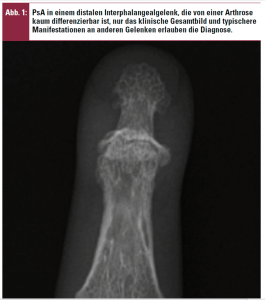

Bei der Oligoarthritis unterscheidet man drei Subformen: den „Strahlbefall“ an Händen bzw. Füßen mit gleichmäßiger Weichteilschwellung (Daktylitis bzw. Wurstfinger oder -zehe), den Transversalbefall (Abb. 1) der Hand- bzw. Interphalangealgelenke oder eine Manifestation am Knie bzw. anderen großen Gelenken.